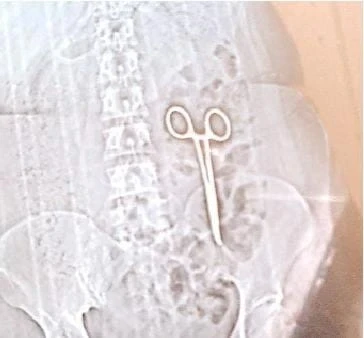

एमपी में लापरवाही की सभी हदें पार, 22 महीने से पेट में कैंची लेकर घूम रही महिला, ऐसे हुआ खुलासा

महिला के पेट में कैंची